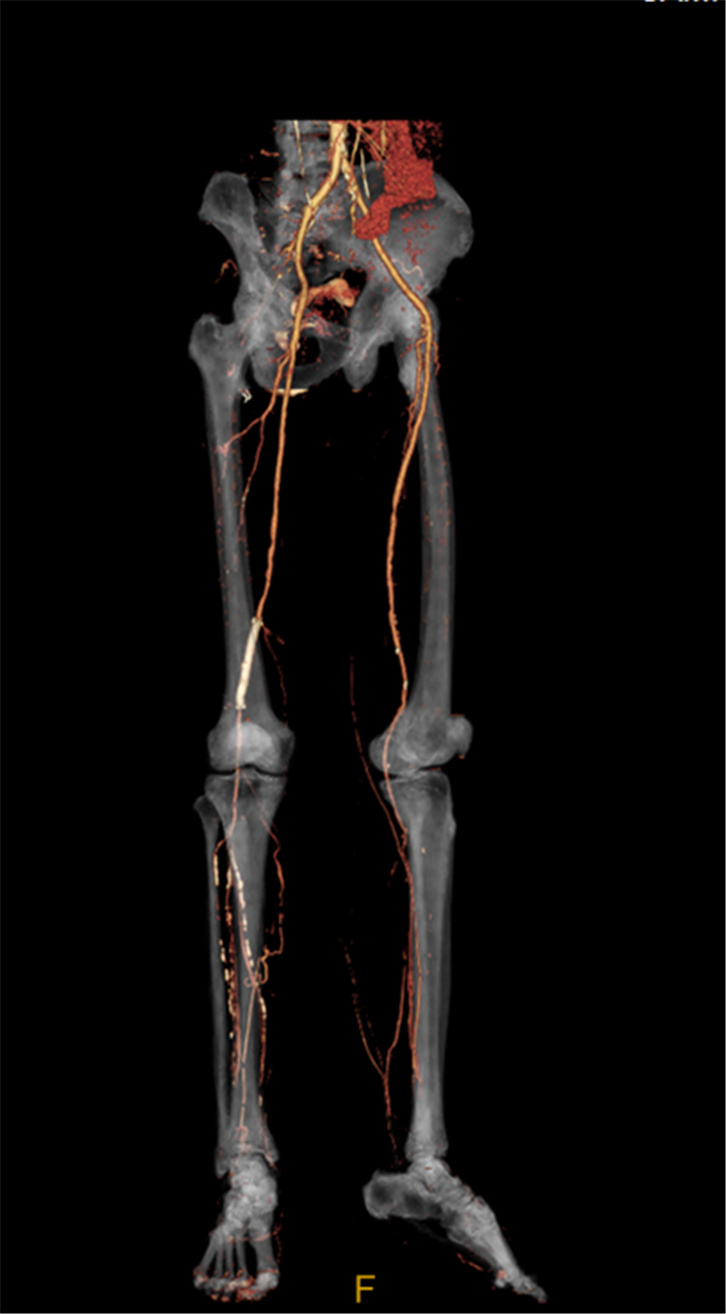

3D精密断层扫描技术可以用于精密三维重建,消除常规断层三维重建中的阶梯伪影,同时可以消除螺旋重建中的风车伪影。

腹部CTA三维重建